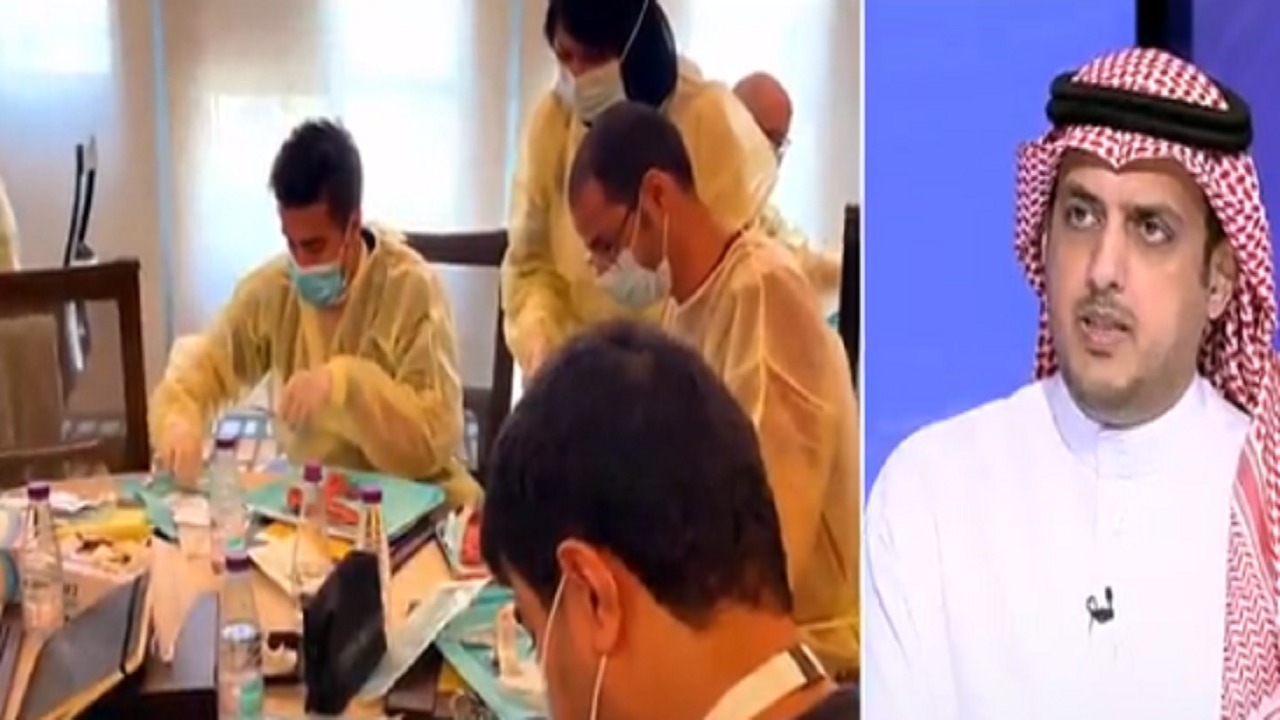

بالفيديو.. استشاري: نسبة الإصابة بتسوس الأسنان تزداد مع العمر

“استشاري”: أمراض الفم واللثة منتشرة في المجتمع السعودي

“سعود الطبية” توضح الفرق بين تسوس الأسنان والتهاب اللثة

المملكة تسجل أعلى معدلات الإصابة بتسوس الأسنان